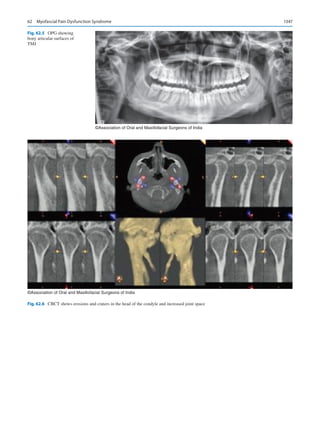

DDS, MD, PhD, Director, Bluestone Center for Clinical

Research, and Professor of Oral and Maxillofacial Surgery at

New  York University pondered about the future of OMS